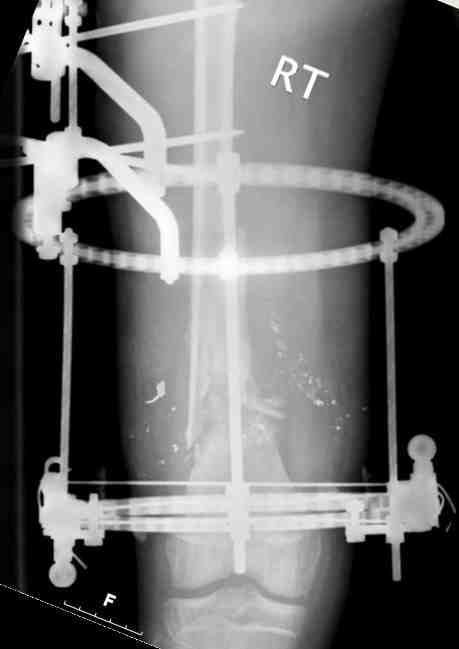

В верхнем ряду показаны рентгенограммы до, после коррекции и после снятия аппарата Илизарова.

On the upper row the X-rays of lt leg before correction, after correction and after apparatus removal have been showed.

В нижнем ряду представлены два снимка после коррекции деформации правой голени. Видно, что качество коррекции не зависит от квалификационного наложения аппарата Илизарова, что было специально произведено для проверки работы программы.

Lower two X-rays – rt leg after deformity correction. As you can see the quality of correction does not depend of placement of Ilizarov Apparatus